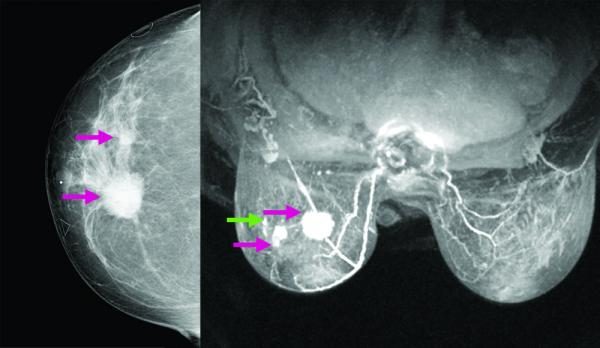

“En una mujer sana, la termodinámica de ambos senos debe ser idéntica. Cuando existen células malignas éstas piden más sangre, más oxígeno y aumentan la temperatura de la región, lo que indica que hay un desbalance”, continúo Estrada.

La muestra estaba conformada por 166 mujeres totalmente sanas, doce con algún tipo de mal en los senos (no canceroso), cuatro con cáncer, y siete que habían sufrido la extirpación quirúrgica de una de las mamas (masectomía parcial). La comparación entre los datos de las mujeres sanas y de las que tienen cáncer les permitió a los científicos adelantar las primeras conclusiones.